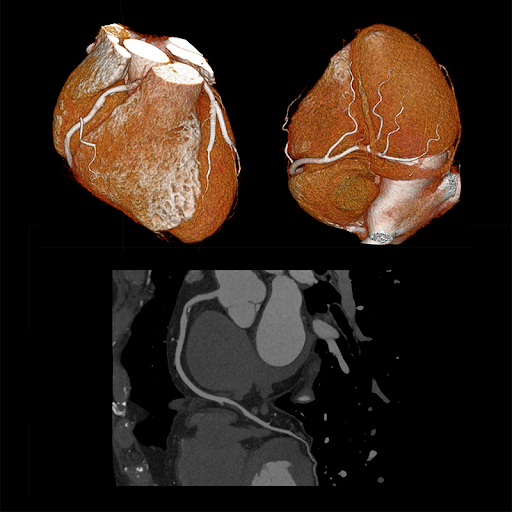

Визуализация сердца